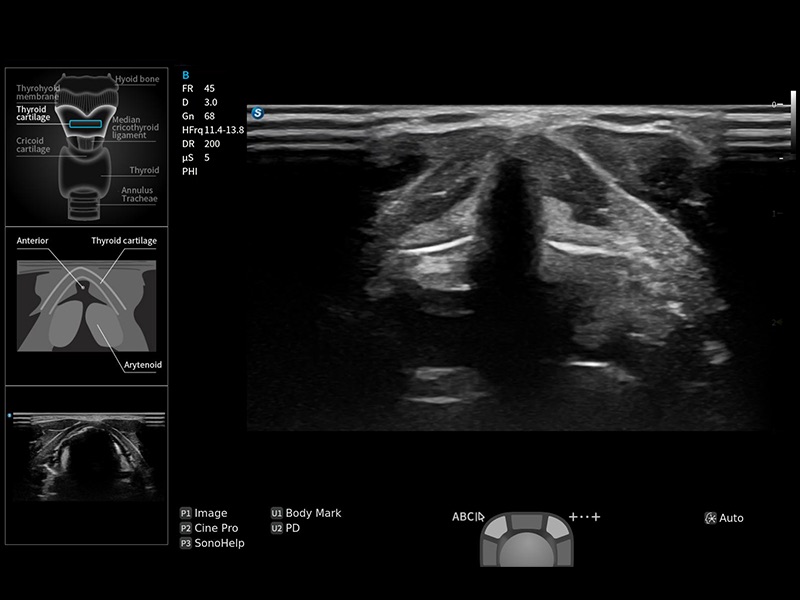

指导操作者进行标准切面的正确扫查,涵盖丰富应用场景,为新晋医生提供实用的参考指导。

将测量、体标和注释等关键内容整合到一个页面中。精简界面,诊断更有针对性。

可助力简化工作流程,同时提升操作标准化程度,并减少按键次数,缩短检查时间。